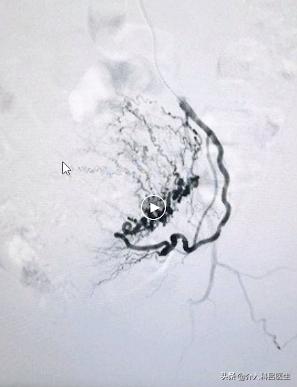

下图分别是左侧和右侧的子宫动脉,这些曲曲弯弯的血管,再栓塞后就消失了。两边的血管都必须要栓塞,这样才能让肌瘤坏死。但是只需要用一根针,整个手术伤口就是一个针眼,出血量就是和你打针输水时出的血差不多,非常的微创。